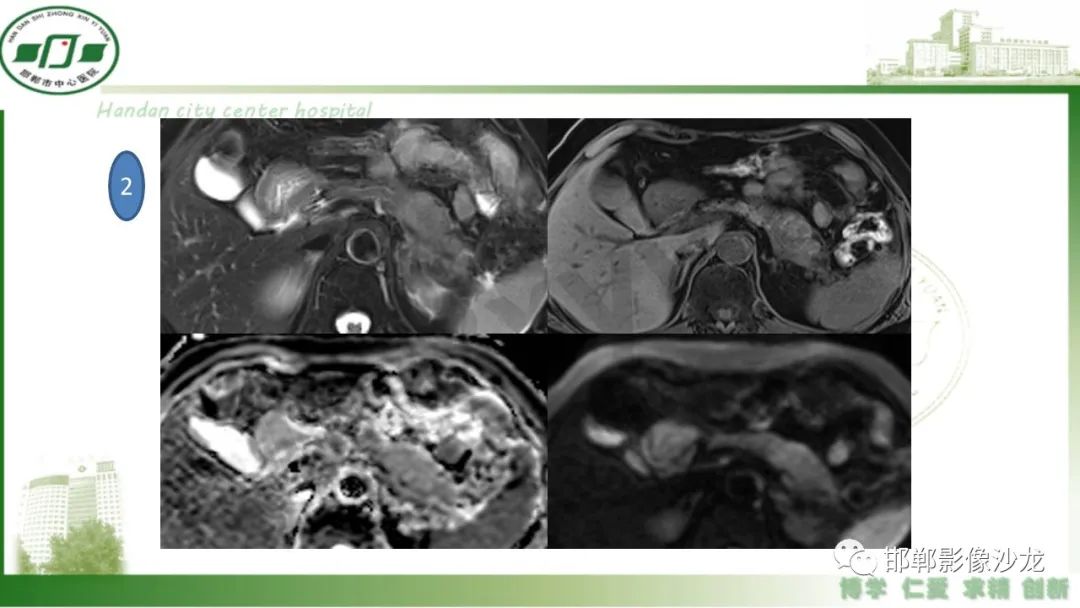

肿块性胰腺炎与胰腺癌的临床、实验室检查、影像学表现有时候很难鉴别,但两者的临床处理、预后又有很大的不同,因此我们平时工作中需要注意两者之间的区别,谨慎诊断,力争为患者及临床带来更大的帮助。